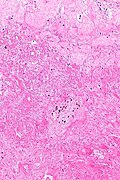

Ovarian infarct, also infarction of the ovary, is an uncommon pathology of the ovary. It may be seen in isolation or in association of benign (e.g. endometriosis) and malignant tumours.

Microscopic

Features: